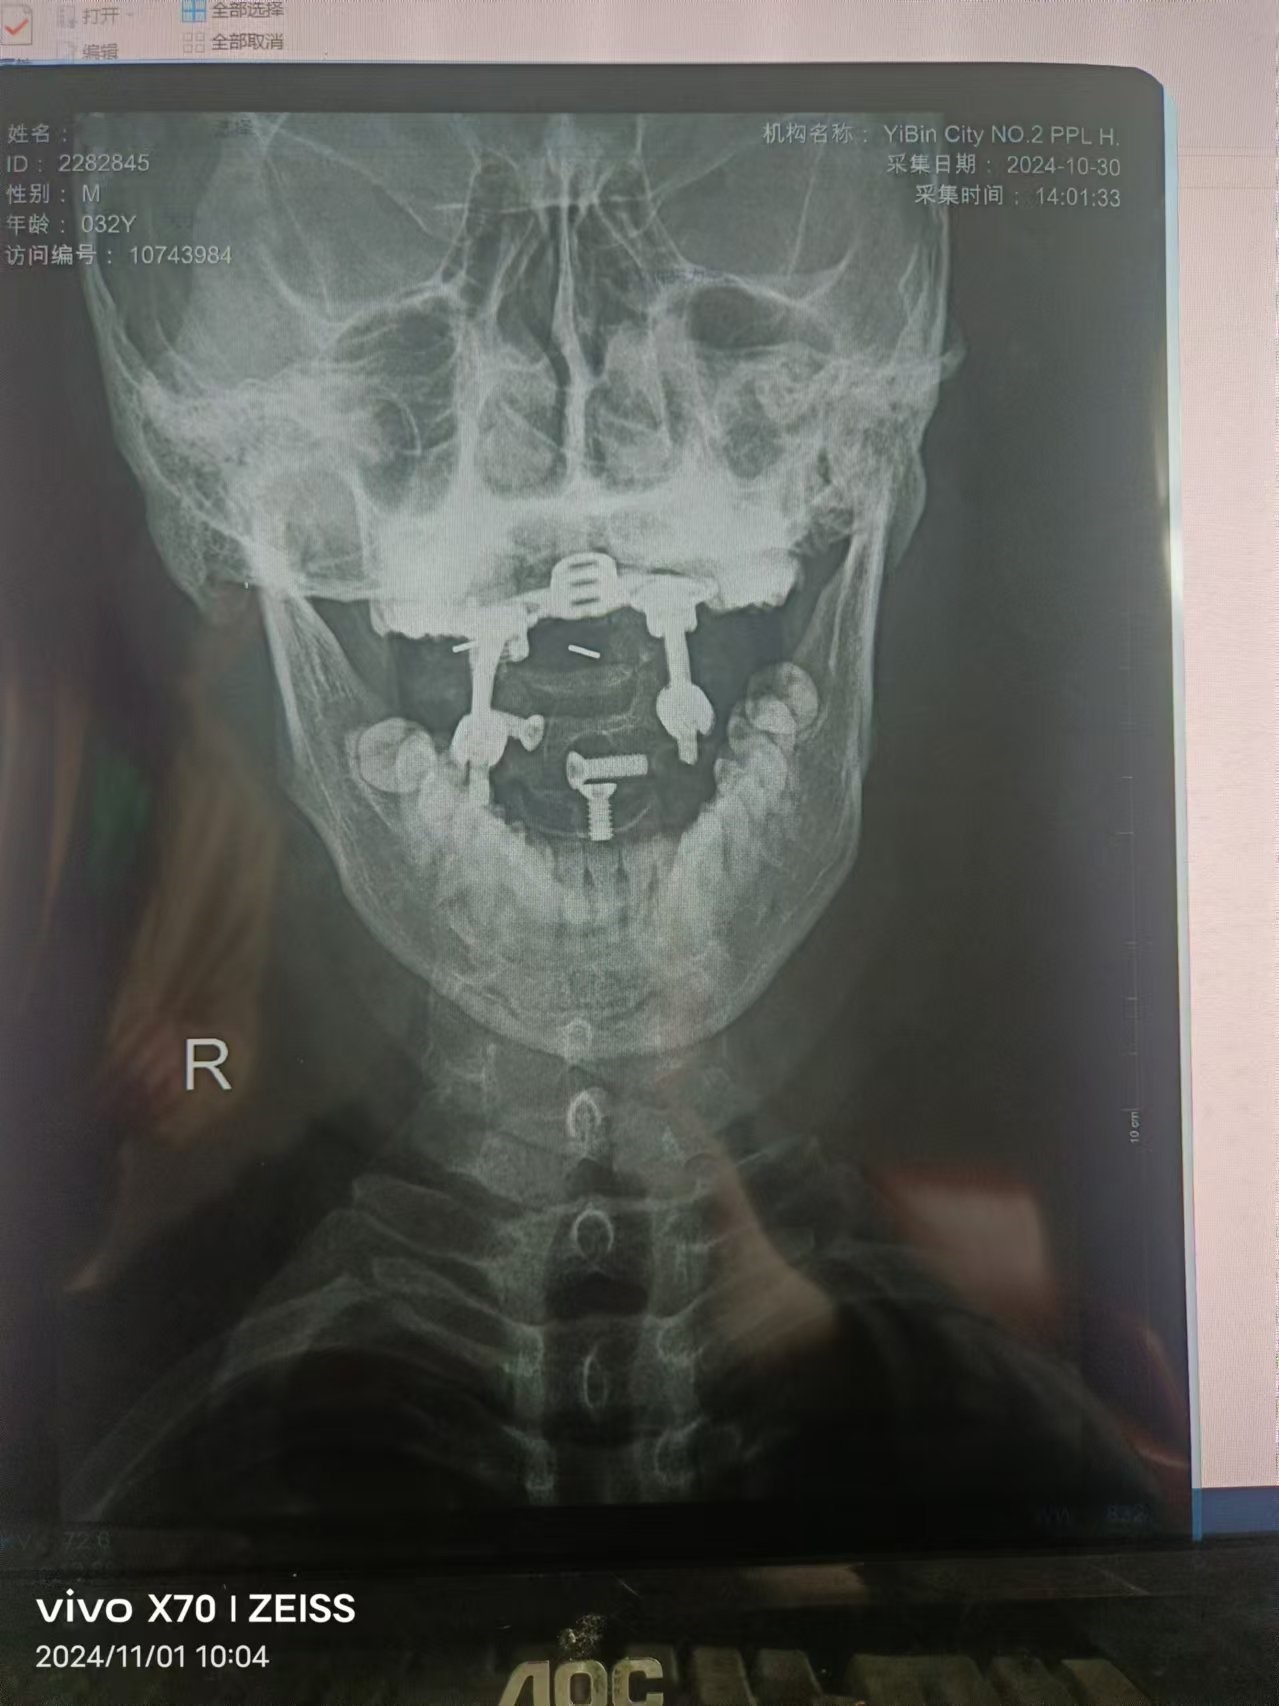

• 2024.10.30,在宜宾二医院复查,螺钉脱离。类似喝醉的头晕,走路不稳,左手力量和灵活度下降,影像如下: